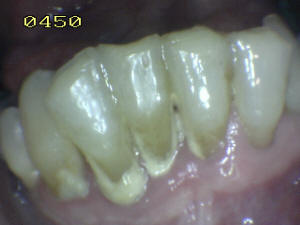

Hay dos zonas críticas, que hay que tener en cuenta para realizar un

cepillado periódico. Una es la cara vestibular (ver foto 1), la cara lingual de los dientes anteroinferiores (ver foto

2 ) y la cara vestibular de los 1ª

molares superiores.